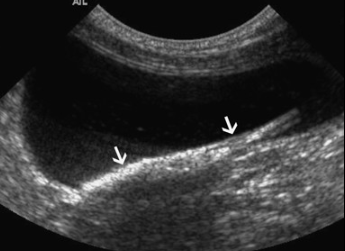

논문이 아직 열리지 않아 내용은 모르겠고 방광에서 발견된 풀씨 케이스의 초음파 사진이니 참고하기 바람